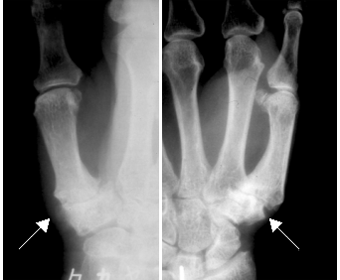

レントゲン検査でCM関節に変形(CM関節の隙間が狭くなる・軟骨が硬くなってトゲの様になる・亜脱臼)が見られた場合に、診断がつきます。